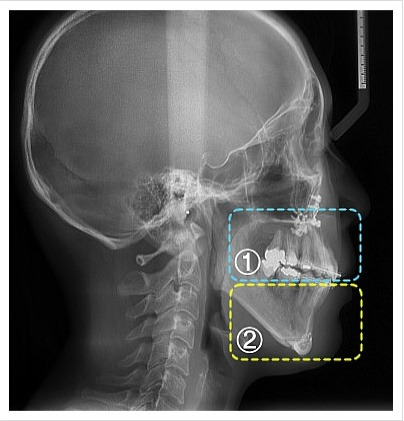

양악수술은 여러 단계로 이루어집니다. 먼저, 환자의 상태를 진단하기 위해 X-ray 촬영과 3D 스캔을 진행합니다. 이후, 수술 계획을 세우고, 수술 당일에는 전신 마취를 시행합니다. 수술 과정은 상악과 하악의 뼈를 절단하고, 필요한 위치로 이동시킨 후 고정하는 방식으로 진행됩니다. 수술 시간은 보통 1~7시간 정도 소요됩니다.

| 양악수술전(옆면) | 양악수술후(옆면) |